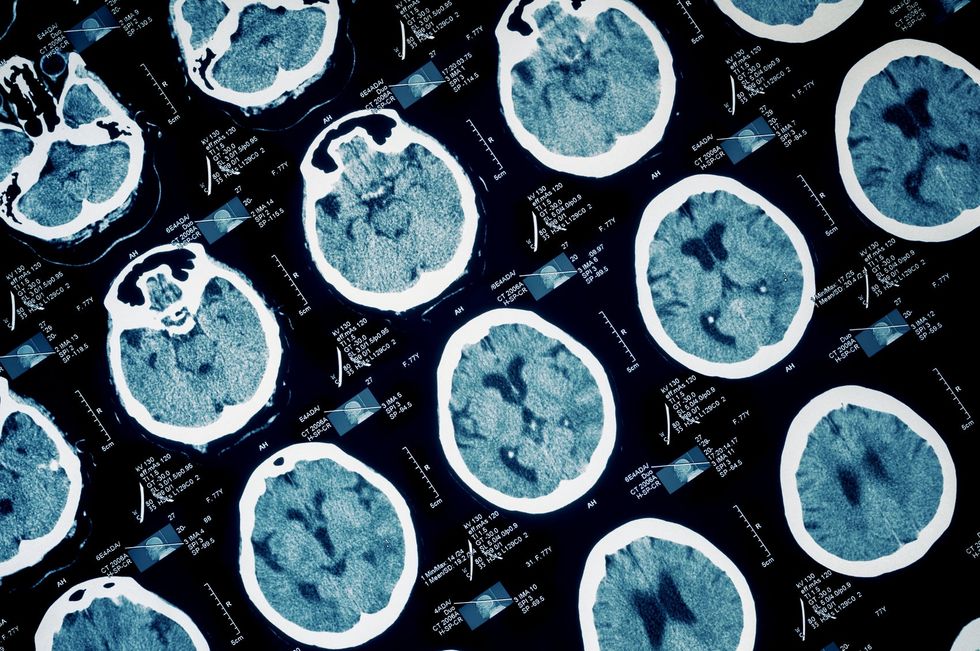

Fallon studied 70 brains and found these factors were common to the psychopathic killers among them:

1. Brain damage

All of the psychopaths that Fallon studied has damage to their orbitofrontal cortex (above the eyes) and to the interior part of the temporal cortex. In addition, all of them had some other of brain damage in a variety of combinations. What kind of psychopathic killer is created from this melting pot of factors is determined by exactly when damage to the brain occurs.